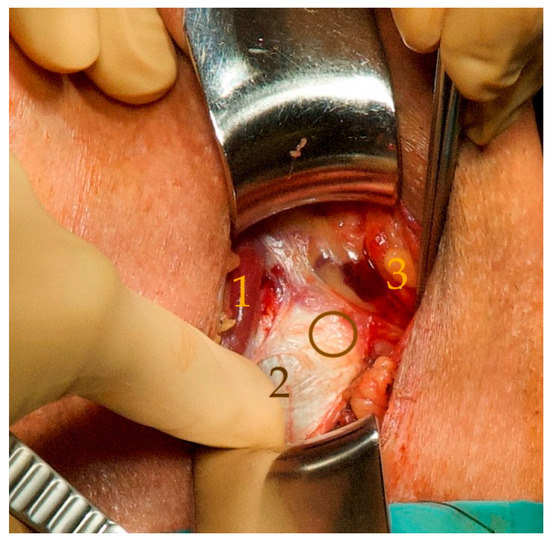

- The perineal central tendon was transected transversely on the bulbospongiosus muscle to allow a partial retrobulbar position of the silicone pad (Figure 2);

- Delivery of the tip of the tunneller paraurethrally below the hiatus urogenitalis, underneath the membranous urethra. As previously described by Rheder et al. for the fixed male Sling Advance, the entrance of the introducer needle tip into the perineal wound should be in the uppermost corner between the inferior pubic ramus and urethral bulb (Figure 5);